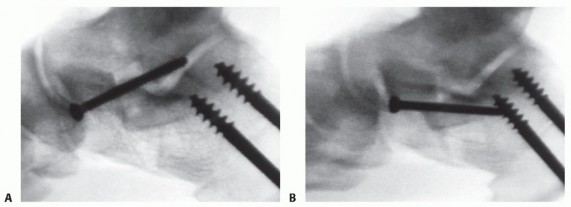

- Angle the fixation screw slightly plantar to avoid placing the screw in the subtalar joint (FIG 6).

FIG 6 • A. Misplaced lateral column screw. B. Corrected position.